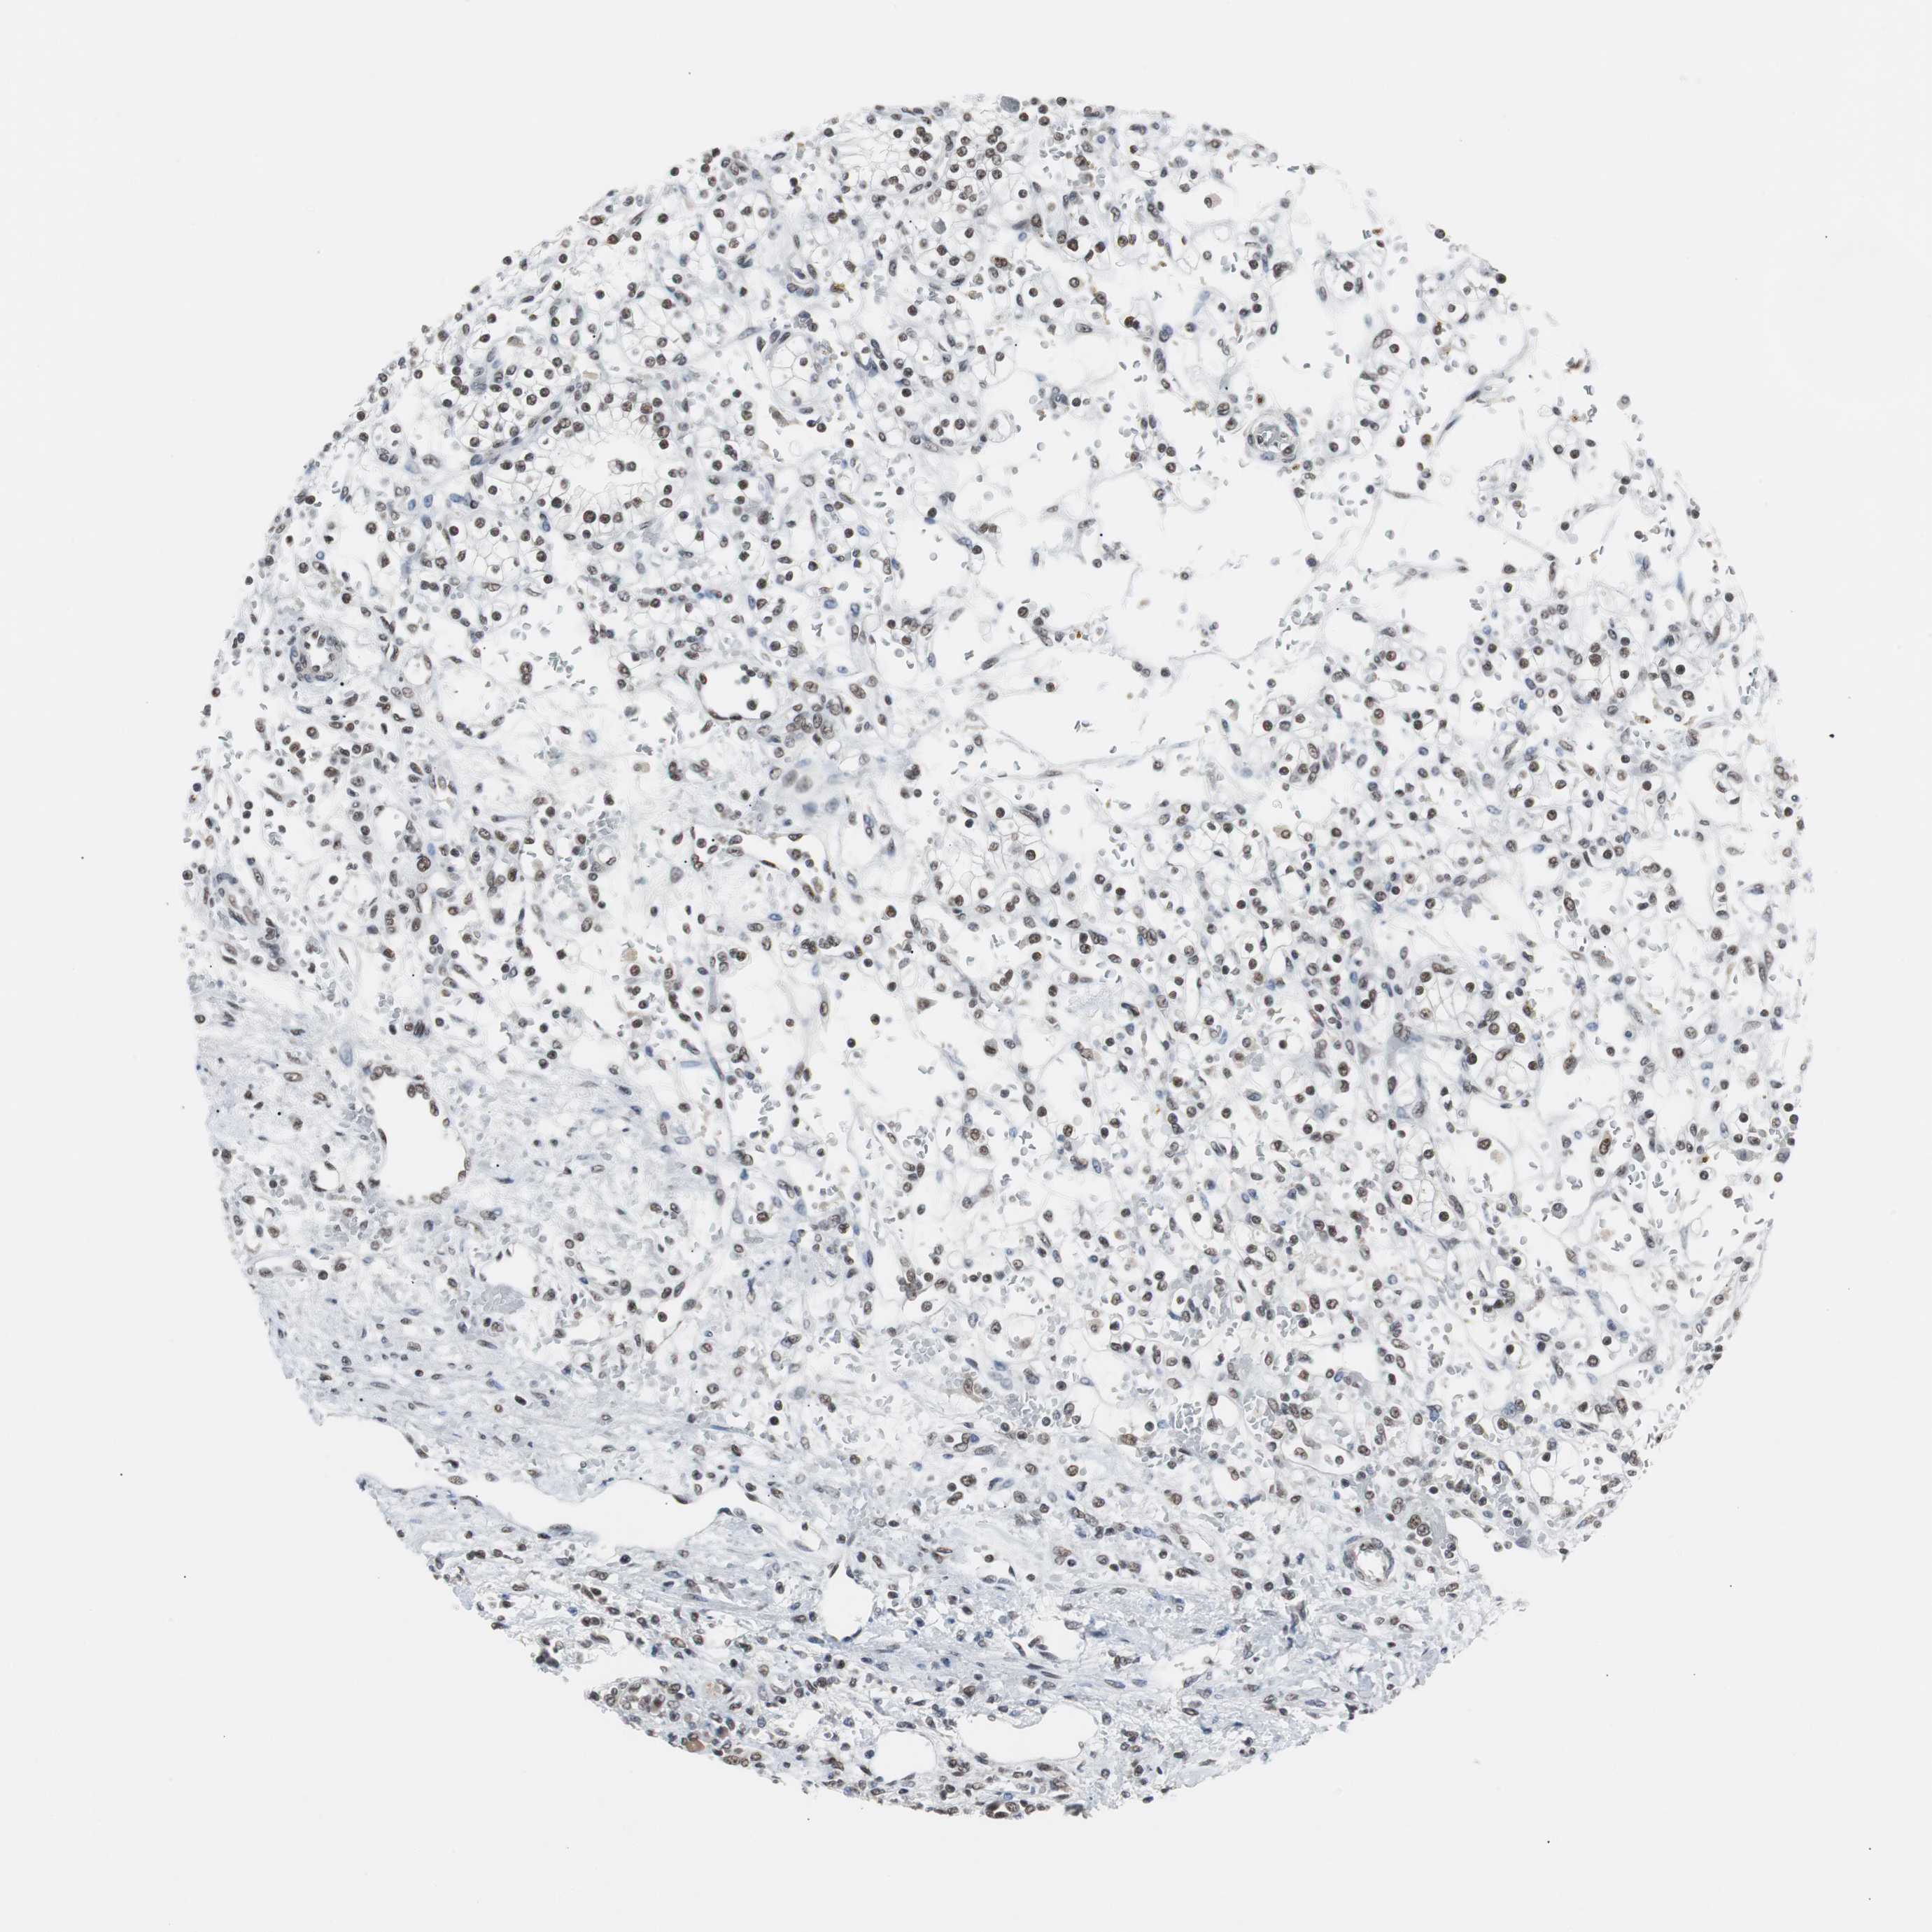

KIDNEY RENAL CLEAR CELL CARCINOMA (TCGA) - Interactive survival scatter ploti

The Survival Scatter plot shows the clinical status (i.e. dead or alive) for all individuals in the patient cohort, based on the same data that underlies the corresponding Kaplan-Meier plots. Patients that are alive at last time for follow-up are shown in blue and patients who have died during the study are shown in red.

The x-axis shows the expression levels (FPKM) of the investigated gene in the tumor tissue at the time of diagnosis. The y-axis shows the follow-up time after diagnosis (years). Both axes are complimented with kernel density curves demonstrating the data density over the axes. The top density plot shows the expression levels (FPKM) distribution among dead (red) and alive patients (blue). The right density plot shows the data density of the survived years of dead patients with high and low expression levels respectively, stratified using the cutoff indicated by the vertical dashed line through the Survival Scatter plot. This cutoff is automatically defined based on the FPKM cutoff that minimizes the p-score. The cutoff can be changed by dragging the vertical line or by entering a cutoff value in the square labeled "Current cut-off".

Under the Survival Scatter plot the p-score landscape (black curve; left axis) is shown together with dead median separation (red curve; right axis). Dead median separation is the difference in median mRNA expression between patients who have died with high and low expression, respectively. It is calculated as follows: median FPKM expression of dead patients with high expression - median FPKM expression of dead patients with low expression. This is intended to aid the user in visually exploring custom cutoffs and the associated p-scores and dead median separation.

Individual patient data is displayed and can be filtered by clicking on one or more of the category buttons on the top of the page. Categories describing expression level and patient information include: high, low, alive, dead, female, male and tumor stages. The scale of the x-axis can be toggled between linear and log-scale by clicking on the "x log" button. Mouse-over function shows TCGA ID, patient information and mRNA expression (FPKM) for each patient.

& Survival analysisi

Kaplan-Meier plots summarize results from analysis of correlation between mRNA expression level and patient survival. Patients were divided based on level of expression into one of the two groups "low" (under cut off) or "high" (over cut off). X-axis shows time for survival (years) and y-axis shows the probability of survival, where 1.0 corresponds to 100 percent.

TAF7 is not prognostic in Kidney Renal Clear Cell Carcinoma (TCGA)

Best expression cut offi

Based on the FPKM value of each gene, patients were classified into two groups and association between prognosis (survival) and gene expression (FPKM) was examined. The best expression cut-off refers the FPKM value that yields maximal difference with regard to survival between the two groups at the lowest log-rank P-value. Best expression cut-off was selected based on survival analysis .

When clicking on this number, the vertical dashed line indicating cut-off, the interactive survival plot, and the Kaplan-Meier curve will be adjusted to show results based on the best expression cut-off.

: 57.58

P scorei

Log-rank P value for Kaplan-Meier plot showing results from analysis of correlation between mRNA expression level and patient survival.

N/A

TCGA RNA samplesi

RNA-seq data is reported as average FPKM (number Fragments Per Kilobase of exon per Million reads), generated by the The Cancer Genome Atlas (TCGA) .

Normal distribution across the dataset is visualized with box plots, shown as median and 25th and 75th percentiles. Points are displayed as outliers if they are above or below 1.5 times the interquartile range. FPKM values of the individual samples are presented next to the box plot.

Average pTPM 83.4

Number of samples 521